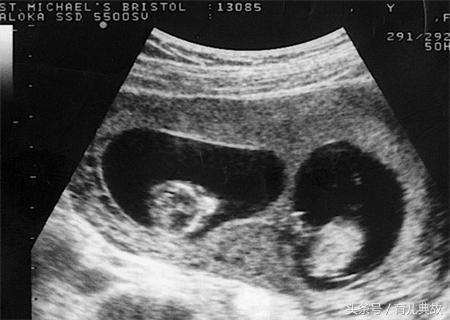

在三个月去医院建卡,B超检查完后说怀的是双胞胎,那一刻就好像中了彩票,三番四次的问医生是不是真的,在听到医生肯定的话,开心的就像中了五百多万。

单胎变双胎的惊喜真的太不可思议了,何其幸运能一次迎来两个宝宝。医生表示,若早期孕囊B超单上出现"宝宝偏大一周/两周"的字样以及HCG值偏高的时候是有可能从单胎变双胎的,在现实生活中也有过不少案例。

当初之所以瞒着有可能是双胞胎,主要是怕孕妇空欢喜一场,现在在看到B超中显示的两个胎芽胎心,就确定了双胎的事实。